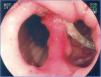

FistulasThe incidence of fistulas in bariatric surgery varies with the technique, the number of patients, and the period analyzed, and whether the case series describe endoscopic or surgical procedures. It was previously estimated from 0.4-26% of the cases21,49,81. However, thanks to surgical improvements, there was a significant decrease in this rate and fistulas are currently estimated to occur in 2.05-5.2% of patients after laparoscopic gastric bypass, in 1.68-2.60% after open bypass, and in 0.6-7% after vertical gastrectomy82–85. This incidence can reach up to 8% when the surgery is performed due to conversion from another technique59. It is one of the most serious complications and is the second cause of death from bariatric surgery, with a mortality rate of up to 1.5%86,87. Fistulas can be gastrocutaneous, internal (gastrogastric or gastroenteric) or they can be considered complex, affecting the gastric pouch and an adjacent or distant organ87. Gastrocutaneous fistula occurs after an early symptom of abdominal sepsis due to peritonitis or localized abscess and is treated with surgical intervention and/or drainage87. Clinical manifestation is late in the gastrogastric or gastrointestinal fistula, with inadequate weight loss or weight regain, epigastric pain (due to marginal ulcer), and reflux, but it can be subclinical, asymptomatic, and with satisfactory weight loss13. Endoscopy defines the presence of the fistulous orifice and characterizes it in relation to its location, size of the internal orifice, and the presence of a foreign body (suture thread) in the adjacent mucosa. Gastrocutaneous fistula occurs more commonly in the gastrojejunal anastomosis and in the upper portion of the suture line of the gastric pouch (bypass) or the gastric sleeve (gastrectomy), adjacent to the esophagogastric transition (fig. 9), most certainly due to a vascularization deficiency at that point14,87. We observed a wide communication in the internal fistula with the intestinal segment or with the excluded stomach (fig. 10). In the 2 locations, distal stricture can be diagnosed, related to the band and the anastomosis in the gastric bypass or excessive angulation at the final portion of the tunneled zone of the vertical gastrectomy. These are considered factors that predispose to and maintain fistulas86. Endoscopy can identify other alterations, such as internal migration of the band in the bypass, tortuosity and dilation of the tubular portion in the vertical gastrectomy, and the presence of mucosal septa adjacent to the fistulous orifice. Contrast-enhanced study of the fistula can be carried out to demonstrate and delimit the fistulous tract, diagnose the communication with other organs, diagnose complex fistulas, and especially, to evaluate emptying difficulty related to the strictures distal to the fistula13,19. Fistulas after bariatric surgeries are treated with nutritional support, suppression of gastrointestinal secretions, treatment of infection, and surgical excision of the fistulous orifice14. Endoscopy can help in these general measures with procedures such as the passage of a nasoenteric tube to enable nutrition, thus excluding transit in the region of the fistula, removal of foreign bodies in the region of the orifice, placement, traction, and repositioning of the drains or probes in the cavities and collections, and especially, treating eventual strictures distal to the fistula84. This type of treatment is of considerable value and enables closure of up to 85% of the fistulas88. Nevertheless, sometimes this approach can be delayed, expensive, or may not achieve the expected success. In such cases, endoscopic treatment specifically directed at the gastrocutaneous fistula that can lead to closure or contribute to a quicker resolution is suggested, reducing hospitalization and morbidity86. Fistula closure can require occlusion, not only of the fistulous orifice, but also of the entire tract. This has been attempted with the endoscopic injection of substances, such as biologic or synthetic glues, placement of an acellular matrix in the form of strips or cones on the tract or at the fistulous orifice, application of endoclips, and in special cases, the placement of self-expanding stents13,14,86. More commonly, a combination of techniques is employed. In order to indicate endoscopic fistula treatment, it is necessary to make sure that the fistula maintenance factor has been resolved, such as infection, foreign body, and distal obstruction. One of the endoscopic fistula treatment options after bariatric surgery is the placement of partially or totally covered self-expanding stents86,89. In the case of post-bariatric surgery fistulas, it is necessary to use special stents that can be removed90. Plastic stents were initially used, followed by metal ones89,90. The covered self-expanding stent forms a physical barrier between the fistula and the endoluminal content, favoring cicatrization, while enabling enteral nutrition91. Poli et al.92, reviewed 67 cases of fistulas after Roux-en-Y gastric bypasses, duodenal switch vertical gastrectomies, and banded vertical gastroplasties treated with stent placement. The results showed fistula closure in 87.7% of the cases, with a range between 79-94% (95% confidence interval). The time interval between stent placement and removal varied between one and 2 months in the majority of studies. Six of the 67 patients (9%) underwent surgical treatment after closure failure with the placement of up to two stents. There was stent migration in 16.9% of the cases, related to stent design or type of surgery and not to the endoscopic placement technique. Endoscopic removal of the stents was possible in almost 92% of the cases and the causes of failure were tissue hyperplasia and migration. There are reports on the difficulty of stent removal, with serious complications such as bleeding, removal in pieces, and even mucosectomy. There are cases of plastic stent placement inside the metallic stent to facilitate its removal93. Considering the difficulties and complications of removal, the migration rate, and the different anatomic details of the surgical techniques, it will be necessary to develop specific stents to be used in post-bariatric surgery fistulas86,91. Even though fistula treatment with stents appears promising, there are not yet enough controlled data to recommend their routine use14,90. These accessories should have differentiated size and caliber (adapted to the surgical anatomy), an anti-migration system, and a safe removal mechanism, or be biodegradable13,86,90. Finally, it appears that the tendency for endoscopy's role in relation to fistulas involves 2 situations: first, in the placement of stents in early cases93, and second, in the rigorous dilation of eventual distal strictures in the chronic cases19. In the cases of gastrointestinal and gastrogastric fistulas, classic treatment is surgical, and the morbidity and mortality can be two times higher than in the first surgery. Taking into account the problems of surgical re-operations, as well as fistula closure failure, endoscopic treatment is suggested. In the last few years, studies with small case series or case reports have shown the possibility of endoscopic suture of these defects, utilizing accessories such as the Endo-Cinch94, special clips (Ovesco)95, StomaphyX96, and Apollo OverStitch97, or the attempt to close the orifice utilizing a stent, biologic glue, debridement through argon plasma coagulation, and sometimes using a combination of two or more methods90. All the techniques have been shown to be feasible, although the durability of these endoscopic sutures needs further evaluation and long-term follow-up, especially in large communications between the pouch and the stomach and/or intestine86,90.